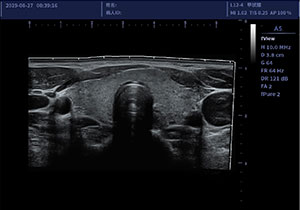

• L12-4/L12-5线阵探头

适用于外周血管、小器官、神经肌骨等

临床超声检查